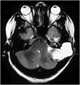

Cholesterol granuloma

Destructive lesion in petrous apex

Erosion of the petrous ridge, pyramid, or apex

Skull base lesion

T1-hyperintense intracranial lesion

T2-hyperintense intracranial lesion